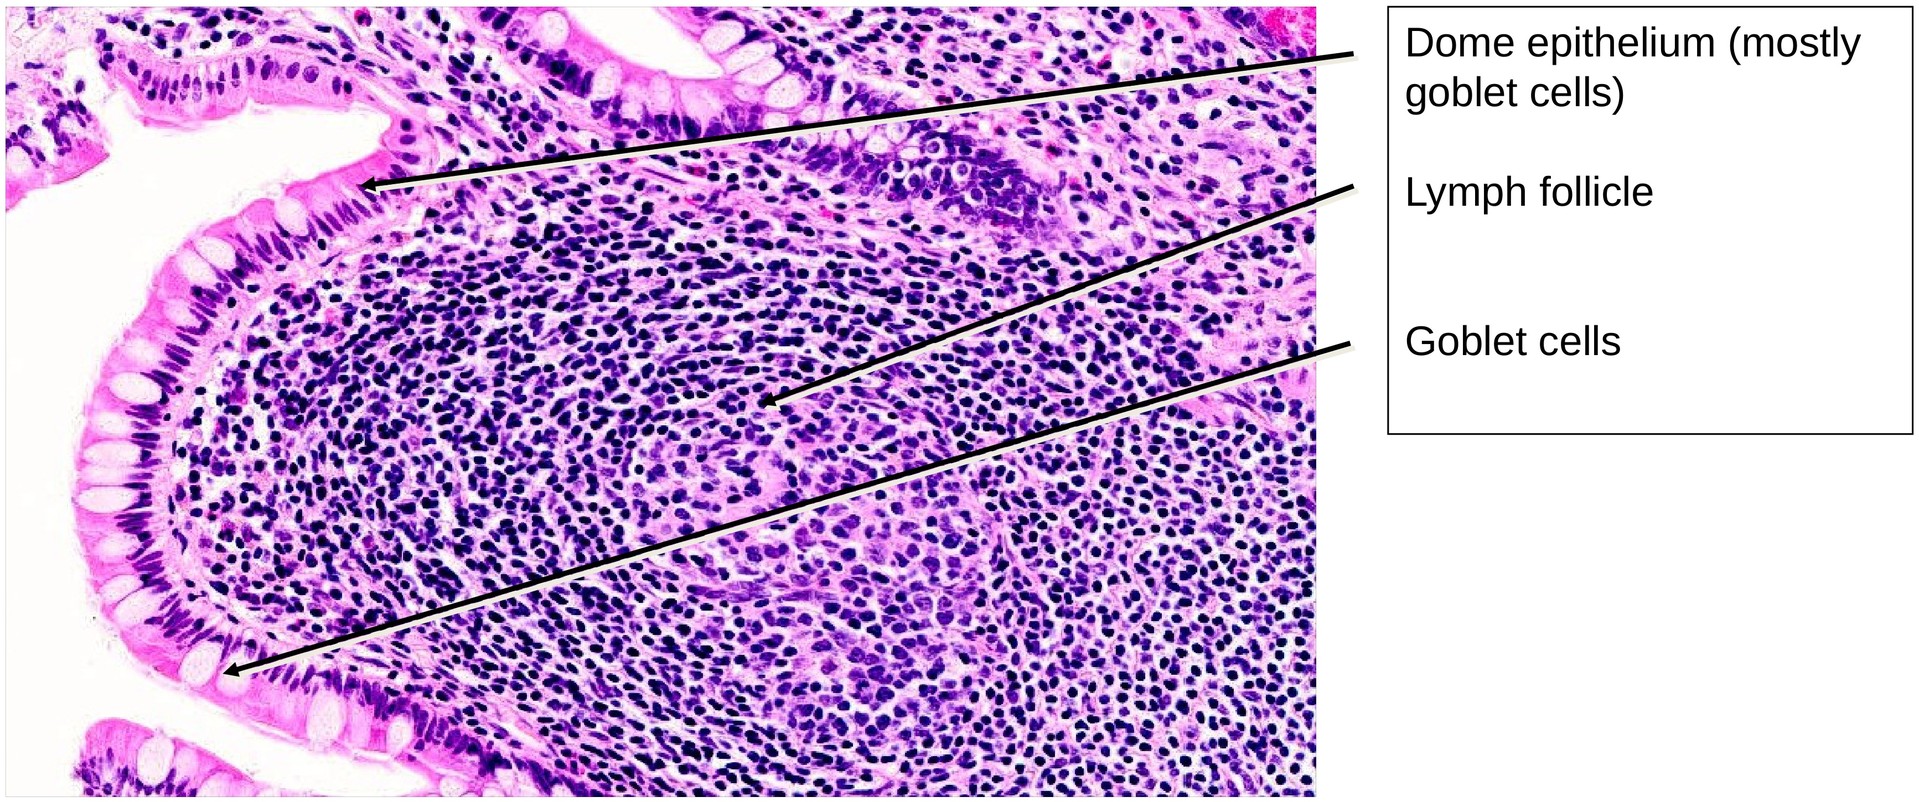

In contrast to the rabbit ileum, where the aggregated lymphoid follicles form a continuous layer (Peyer’s patches) on the antimesenteric side, in the human ileum these follicles are more irregularly distributed along the mucosal folds. Together, they form part of the gut-associated lymphatic tissue (GALT).

The epithelium covering the lymphoid follicles is termed the dome epithelium. Unlike the adjacent mucosa, this epithelium lacks villi and crypts. Within it, a few M cells (microfold cells) can be identified among the enterocytes; these specialized cells facilitate antigen transfer to the underlying immunocompetent lymphoid cells.

- Locate the lymphoid follicles and observe their germinal centers (reaction centers).

- Search for M cells within the dome epithelium covering the lymphoid follicles.

- Note that in the area of the dome epithelium, villi and crypts are absent.